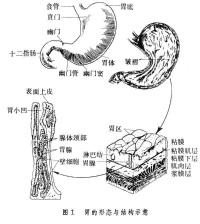

1.慢性浅表性胃炎又称慢性单纯性胃炎胃粘膜最常见的病变之一,国内胃镜检出率高达20%~40%,以胃窦部常见;胃镜见胃粘膜:胃粘膜充血、水肿,呈淡红色,可伴点状出血及糜烂,表面可有灰黄色或灰白色粘液渗出物覆盖;显微镜示:病变位于粘膜浅层;

2.慢性萎缩性胃炎根据发病是否与自身免疫有关及是否伴有恶性贫血,分为A、B型;A型属于自身免疫性疾病,患者抗壁细胞抗体(PCA)及抗内因子抗体(IFA)阳性,并伴有恶性贫血,病变主要位于胃体和胃底部;B型多见于胃窦部,无恶性贫血;两者胃粘膜改变相似;胃镜见胃粘膜:由正常的橘红色变为灰色或灰绿色,粘膜层变薄、皱襞变浅甚至消失、粘膜下血管透见,表面有细颗粒、偶见出血糜烂;显微镜可见淋巴细胞、浆细胞浸润、肠上皮化生、腺上皮化生、不典型增生;